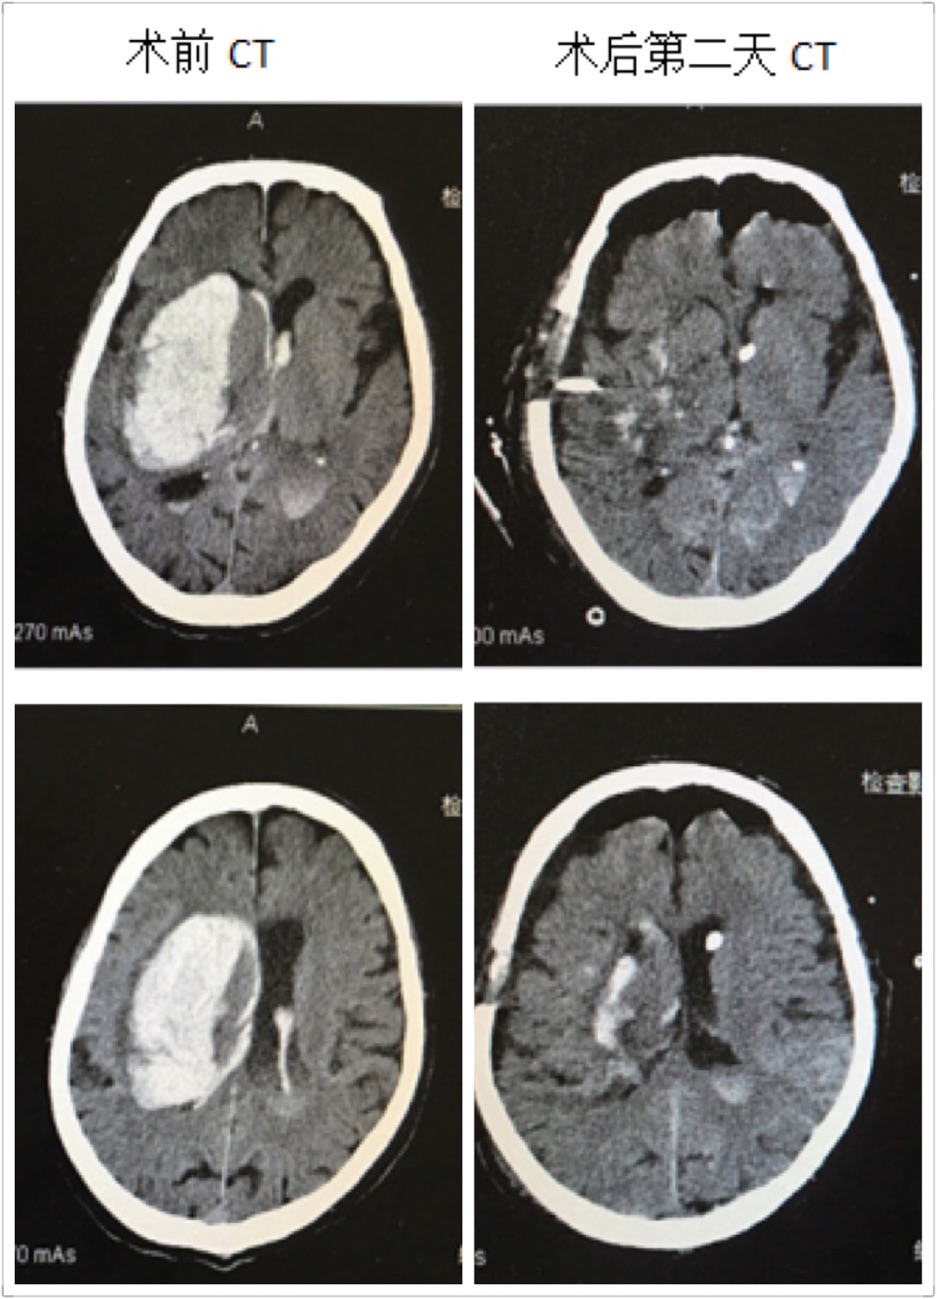

近日,啄木鸟 神经外科成功救治一名高龄脑出血患者,并顺利康复出院,取得了满意的疗效。这位男性患者86岁,出血量约120ml,入院后处于深昏迷状态,Glasgow评分仅3分,一侧瞳孔散大,颅内高压频繁喷射性呕吐,病情危重,随时有死亡的可能。在这例高龄脑出血患者入院后,啄木鸟 神经外科王钢副主任医师放弃休息时间,立即组织医疗小组,商讨治疗方案,像这样大量脑出血手术必须手术治疗。在保证血肿清除率及创伤小、出血少的前提下,在我科完成多例神经内镜下血肿清除术的基础下,王钢副主任医师提出:这位高龄患者可以采取小骨窗和神经内镜下清除血肿。

在王钢副主任医师的带领下,和麻醉科曹淑梅主任,杨克副主任一起,经过详细的术前讨论,制定周密的手术方案,急诊在全身麻醉下行脑出血小骨窗及神经内镜下清除血肿。手术十分顺利,手术历时2小时,骨窗大小直径约3cm,术中完全清除血肿,出血极少,术中未输血。术后第2天患者意识状态明显好转,由昏迷转为呼唤睁眼,出院时患者意识已经清醒,并且能够正常交流。